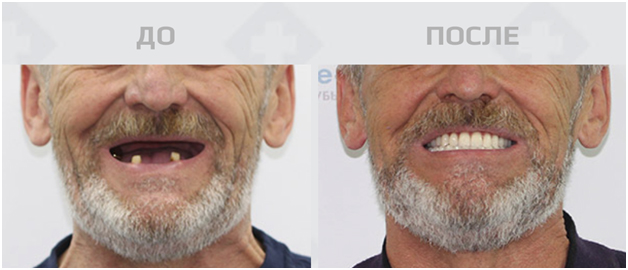

Полная или почти полная адентия, то есть отсутствие зубов — распространенная проблема 21 века. «Болезнь» с каждым годом молодеет, виной тому множество факторов. Это и меняющийся образ жизни, и состояние экологии. Именно вредные вещества оказывают на состояние зубов колоссальное влияние. К счастью, медицина тоже не стоит на месте и оперативно успевает за нарастающей проблемой. Сейчас в арсенале у специалистов — современные технологии и инновационные способы, которые помогают подарить обворожительную улыбку тысячам людей. Самый действенный на данный момент метод — это именно имплантация зубов.

Лишних хлопот можно избежать, если воспользоваться услугами проверенной клиники и провести имплантацию по протоколу немедленной нагрузки. Это значит, что пациенту установят несъемный зубной протез в течение 2-3 дней после вживления имплантатов. Уникальность в том, что жевательная и эстетическая функции зубов будут восстановлены полностью почти мгновенно. Как правило, костная пластика при таком методе не требуется. Так весь процесс лечения вместе с подготовкой займет не более одной недели.

Имплантация — то, на что бывает сложно решиться, но большинство после процедуры признаются, что зря откладывали поход к врачу так долго. Буквально за несколько дней удастся обзавестись ослепительной улыбкой, снова почувствовать вкус любимой пищи и вернуть себе незабываемое ощущение здоровья полости рта. Реабилитация при удачном исходе проходит максимально быстро. Это важно в том числе — для работающего населения. Для того, чтобы сделать имплантацию, не придется бросать дела или брать долгосрочный отпуск.